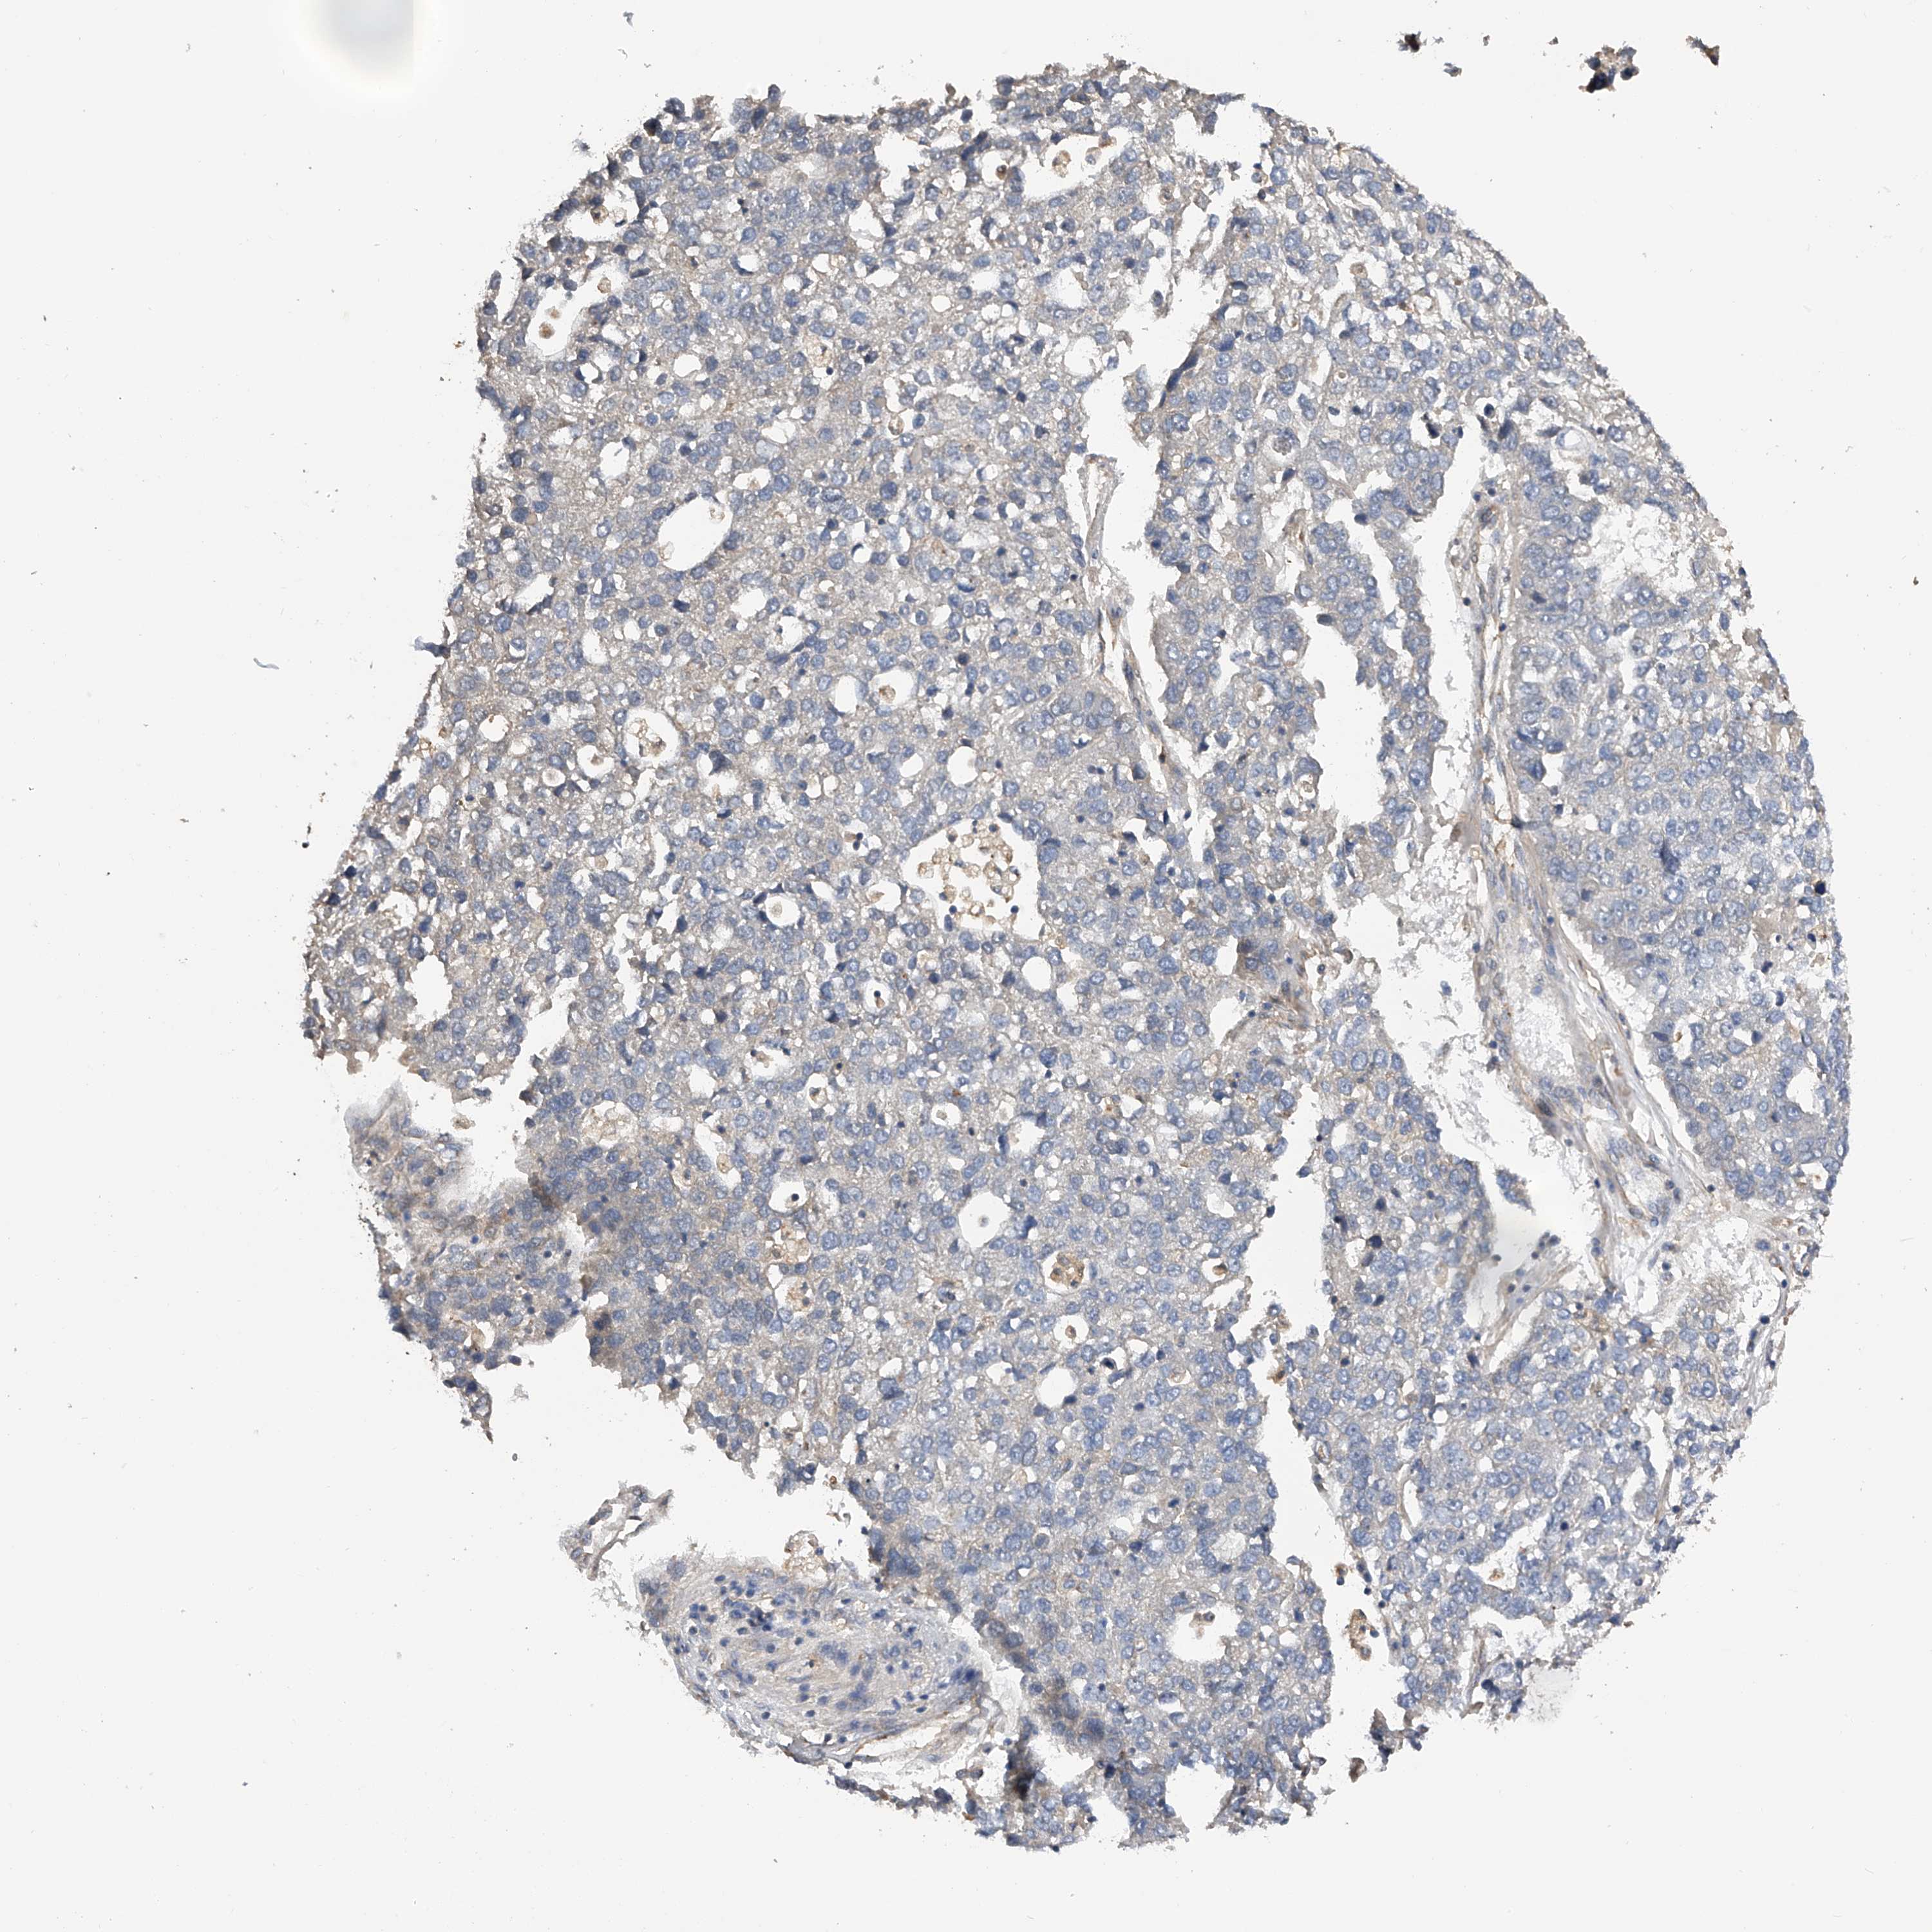

PANCREATIC CANCER - Protein expressioni

A mouse-over function shows sample information and annotation data. Click on an image to view it in a full screen mode. Samples can be filtered based on level of antibody staining by selecting one or several of the following categories: high, medium, low and not detected. The assay and annotation is described here.

Note that samples used for immunohistochemistry by the Human Protein Atlas do not correspond to samples in the TCGA dataset.

Antibody stainingi

Antibody staining in the annotated cell types in the current human tissue is reported as not detected, low, medium, or high, based on conventional immunohistochemistry profiling in selected tissues. This score is based on the combination of the staining intensity and fraction of stained cells.

Each image is clickable and will lead to virtual microscopy that enables deeper exploration of all samples and also displays staining intensity scores, fraction scores and subcellular localization as well as patient and tissue information for each sample.

Antibody HPA029412

Antibody CAB034366

Staining

High

Medium

Low

Not detected

Intensity

Strong

Moderate

Weak

Negative

Quantity

>75%

75%-25%

<25%

None

Location

Nuclear

Cytoplasmic/membranous

Cytoplasmic/membranous,nuclear

Adenocarcinoma, NOS